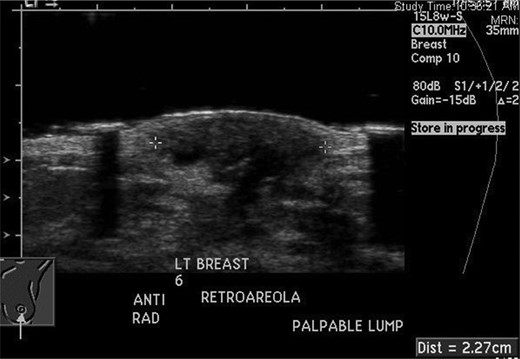

The excisional biopsy was performed in June 2012, which revealed a diagnosis of leiomyosarcoma (slides seen in Figs. 3–5).

Immunostain with SMA (smooth muscle actin). Positive cytoplasmic staining indicating smooth muscle origin.